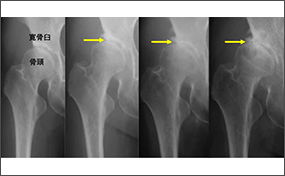

発育性股関節形成不全に関わる遺伝子座を同定(共同プレスリリース)

理化学研究所生命医科学研究センターゲノム解析応用研究チームの吉野宗一郎客員研究員(九州大学大学院医学研究院整形外科学分野助教)、寺尾知可史チームディレクター(静岡県立総合病院免疫研究部長、静岡県立大学特任教授)らの共同研究グループは、大規模な全ゲノム関連解析(GWAS)を行い、発育性股関節形成不全(Developmental Dysplasia of the Hip:DDH)とこれに続発する変形性股関節症(Hip Osteoarthritis:OA)の発症に関わるゲノム上の新しい疾患感受性領域(遺伝子座)を同定しました。

発育性股関節形成不全の遺伝的リスクが変形性股関節症発症へ与える影響を解明(共同プレスリリース)

九州大学大学院医学研究院の吉野宗一郎大学院生、中島康晴教授、山口亮介助教、田中秀直大学院生、理化学研究所の寺尾知可史チームリーダー(静岡県立総合病院免疫研究部長、静岡県立大学特任教授)、同センターの池川志郎チームリーダー(研究当時)らの共同研究グループは、発育性股関節形成不全の患者様から聴取した詳細な家族歴や発症年齢、治療歴などの情報を解析し、発育性股関節形成不全の遺伝的リスクが強いほど変形性股関節症の発症や進行が早まることを明らかにしました。